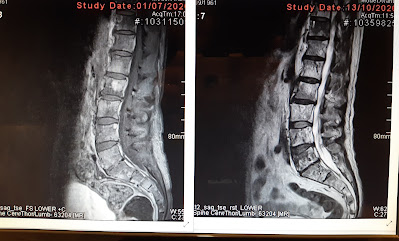

brain or spine MRI, chest and body CT, specific blood tests…

Imagine our feelings of disbelief, when the registrar told us that cancer in the spinal column has resulted in a broken vertebra and that compared to the first imaging at the start of July, the Leptomeningeal (LM) disease continues to be a major cause of concern.

On entering, the oncologist chatted with Geoff whilst checking the diplopia. Only a narrow region of single vision can be identified. Even so, the oncologist has been impressed with Geoff’s overall clinical improvement. Addressing the scan results, he suggested that the LM disease may have worsened after the July scan and before the targeted drug therapy began to have an effect. Likewise, the broken vertebra may be evidence that the drug is attacking cells in the bone tumors, some of which may have been holding the bone together.